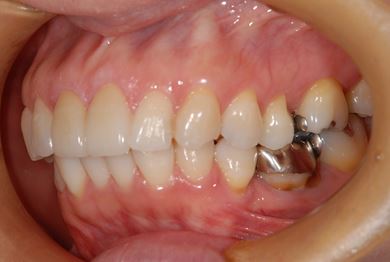

治療後

• 治療後

治療内容 オールセラミッククラウン2本(オールセラミック用土台2本)

総治療費 301,875円

治療期間 2ヶ月